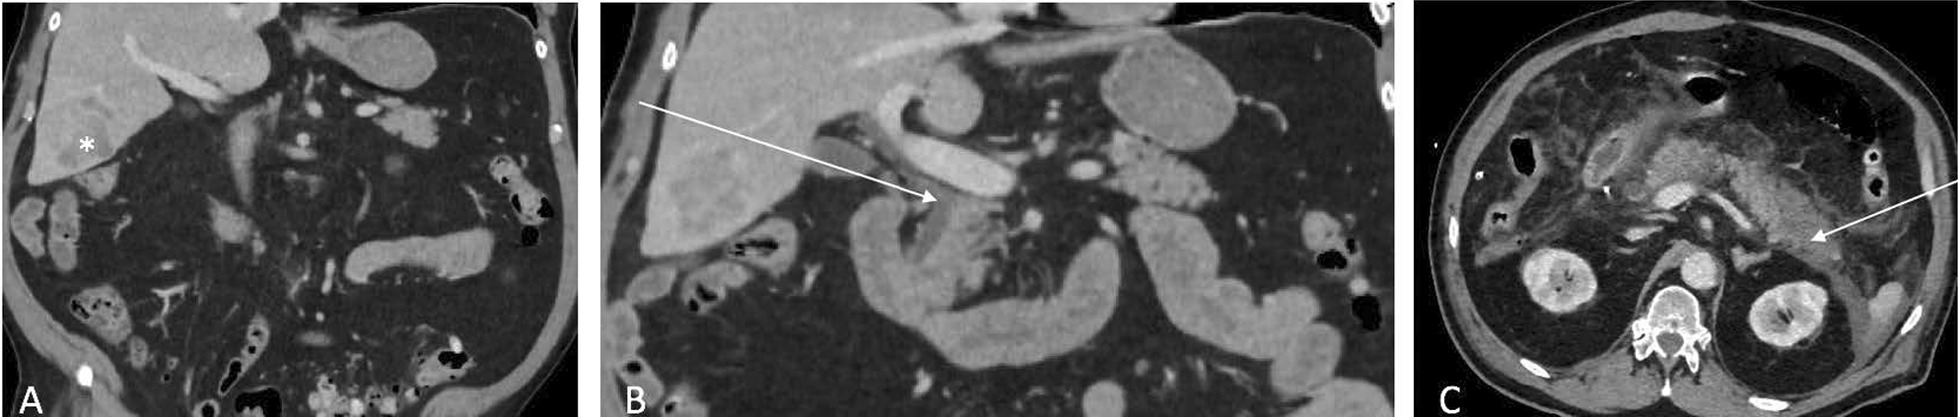

Fig. 1.

Patient A. A Preoperative CT showing HCC in segment VI (white asterisk). B Preoperative CT, distal implantation of the cystic duct (white arrow). C CT scan at POD 1 showing necrosis of the tail of the pancreas t